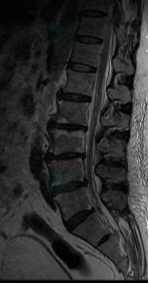

入院后给予逐级止痛治疗,但症状无明显缓解;为更加详细明确病因及病变位置,拟行腰椎MRI、左髋关节MRI及全身骨扫描等相关检查,但患者因剧烈疼痛无法平躺配合,为解决这一难题,遂邀请我院麻醉科会诊,在麻醉科谭敬老师、袁伟老师、宋珂珂老师的积极努力下,成功完成硬膜外麻醉并置管,患者疼痛症状明显缓解,使得检查顺利进行,结果显示:MRI检查示腰2/3椎体信号异常,再结合抽血检验示结核杆菌T细胞检测阳性这一指标,遂考虑病变部位可能为腰2/3结核感染可能。为进一步明确病变责任部位,于局麻下为该患者行腰3神经根封闭术,封闭后病人症状明显缓解,证实了先前诊断。杨益民副主任医师与患者及家属充分沟通后,决定采用微创椎间孔镜手术方式给予患者行结核病灶清除、神经根探查松解术,手术过程顺利,术后病人症状完全缓解,病人及家属对我院诊疗水平表示十分满意。

腰椎MRI示:腰2、3椎体信号异常,椎管内异常信号影